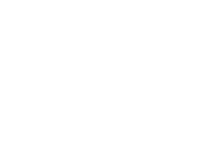

2. Megemelkedhet a koleszterinszint.

Ha azt hiszed, a koffeinmentes kávé segít majd a koleszterineden, alaposabban meg kell nézned, hogy milyen babból készült a kávéd. A kutatások kimutatták, hogy a koffeinmentes kávé jelentősen növeli a káros koleszterin szintjét, ennek oka pedig a kávébabok szelekciójában keresendő. A legtöbb koffeinmentes kávé robusta kávébabból készül, aminek magasabb a zsírtartalma, ezért növeli a koleszterint. Ha hagyományos kávé helyett koffeinmenteset szeretnél inni, olyat keress, ami arabica kávébabból készült.